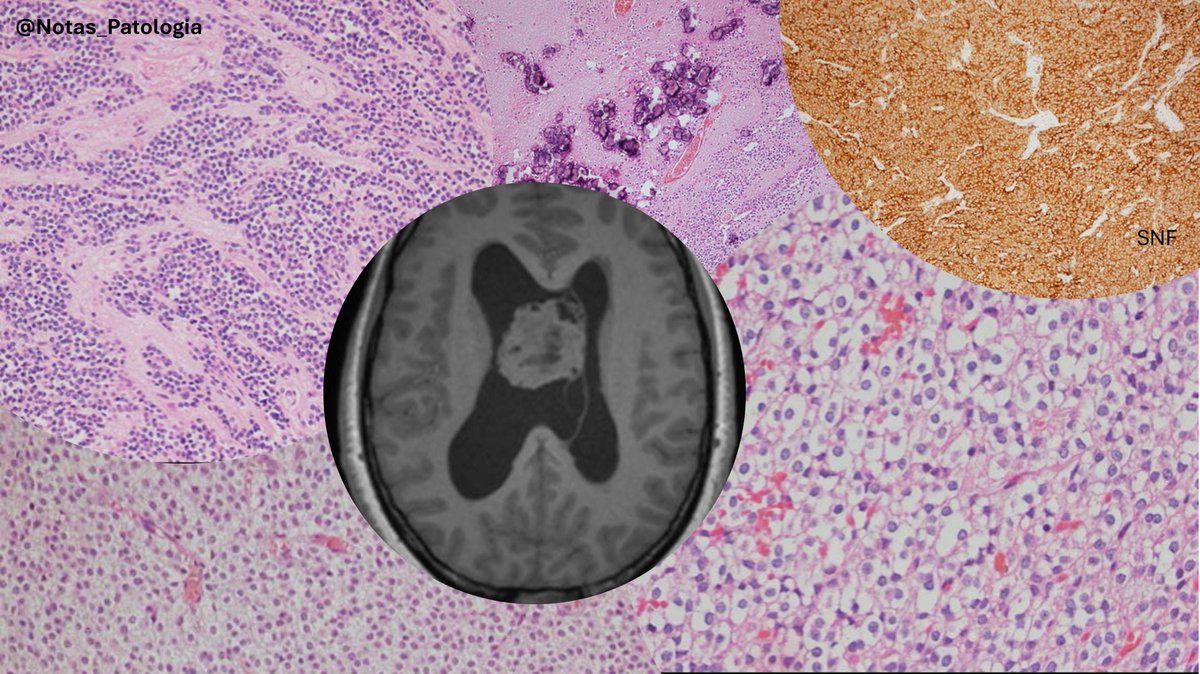

@Notas_Patologia

5 months

🔬 #NeurocitomaCentral: A rare intraventricular tumor with neuroepithelial flair 📷 Quick definition: Rare, well-differentiated intraventricular neoplasm with neuroepithelial differentiation, typically near the foramen of Monro, comprising 0.1–0.5% of primary CNS neoplasms. 📷Key